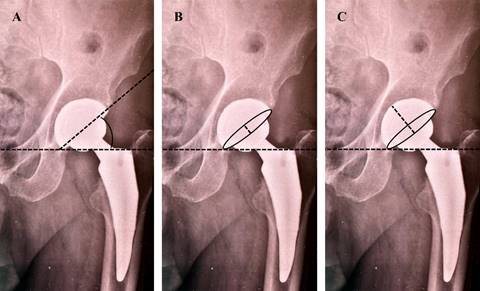

Las imágenes radiográficas se visualizaron en el sistema de imágenes médicas CareStream donde se obtuvieron los ángulos de inclinación y anteversión con el método de Widmer, el cual consiste en la medición del eje corto y largo de hemiesfera acetabular, usando la fórmula arcsin (eje largo/eje corto); posteriormente se obtiene la inclinación del componente, tomando como referencia una línea horizontal interlagrimal o interisquiática y el borde externo de la copa, la relación entre estos datos en la Tabla de valores establecida nos proporciona el ángulo de anteversión; al no contar con un software, imágenes tridimensionales, navegación, etcétera, no se compara con ningún otro método de obtención de la versión acetabular ni comparación entre mediciones transoperatorias (Figura 1), se toma como valores de referencia para definir si se encuentra dentro de la ZSL (inclinación 30o-50o; anteversión 5o-25o).